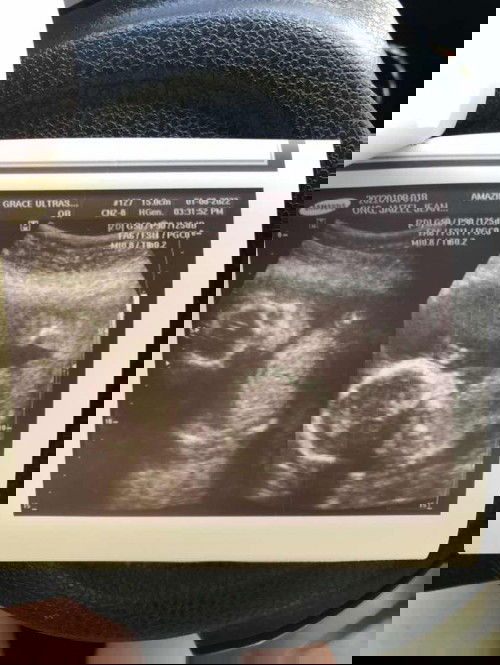

Gender guessing

Hi mom's What gender do you think ? This is my 3rd ultrasound pero hindi padi ng papakita si baby ng private part laging ng tatago . 🥺 gusto ko na malaman ano tingin niyo ?